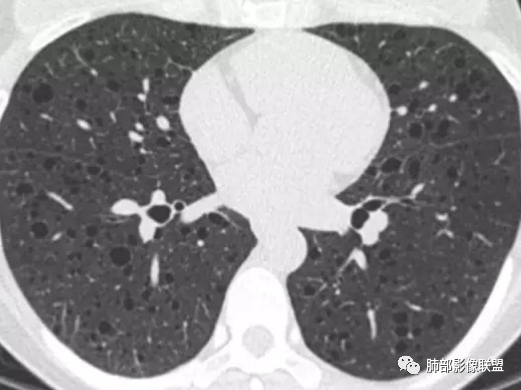

胸部CT:两肺多发囊腔,中上肺受累为主,囊腔形态不规则(囊有点丑),分叶状,囊壁厚薄不均,大部分囊壁薄。尚有一些结节影。

1.LAM  临床表现为进行性呼吸困难、反复发作性气胸、咯血、乳糜胸,多见于育龄期妇女,囊腔长得漂亮,囊腔之间肺组织正常。

晨读病例囊长得不漂亮,也没有呼吸困难等症状,不怎么支持LAM。

4.PLCH:常见于吸烟青年男性,囊腔形态不规则,呈分支状,囊壁厚薄不均,双侧肋膈角常不受累。

晨读囊不规则,分叶,存在PLCH可能,但为不吸烟女性,可能性下降。